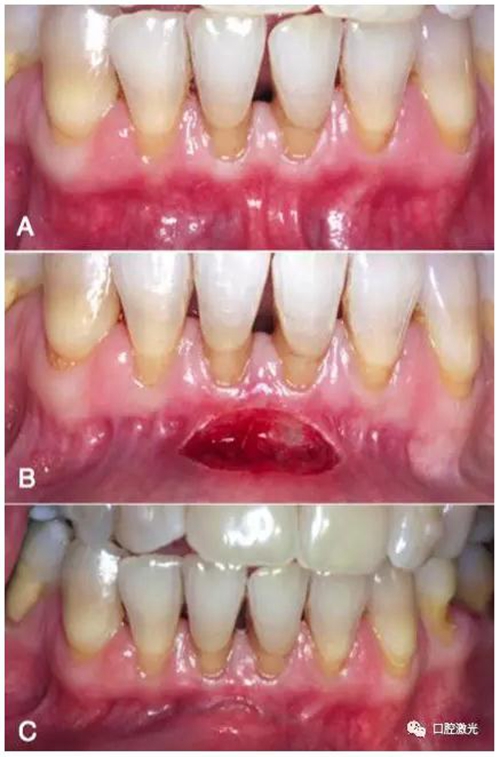

A:下唇系帶手術(shù)前

B:下唇系帶手術(shù)完成現(xiàn)場

C:手術(shù)完成一周后迅速恢復(fù)狀態(tài)